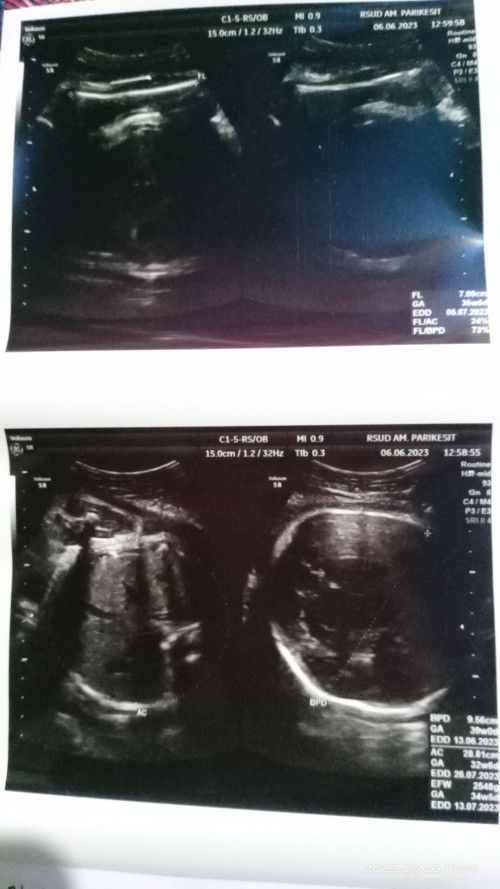

HPL 11 Juni

Hpl 11 juni, kontrol sekalian usg tgl 6 juni kemarin si adek belum masuk panggul kata dokter baru mau masuk panggul. Ari² adek dicek udah mulai tua karena air ketuban masih cukup disuruh dokter tunggu 1 minggu lagi. kalau sampai tgl 12 ini gk ada tanda, tgl 13 terpaksa harus induksi 🥺 Tgl 7 besoknya, pagi keluar lendir coklat dibarengi rasa kram perut cuma jaraknya yg masih jauh jedanya, dikira mau pembukaan pas dicek ke bidan masih tebal dinding rahimnya dan belum ada pembukaan sama sekali. Tapi alhamdulillah kata bidan adek udah masuk panggul 🥹sampai hari ini kdng keluar lendir coklat disertai rasa mules ringan aja belum ada tanda lendir darah Mohon doanya ya bunda, semoga saya disegerakan mendapat gelombang cinta adek sebelum tgl 12 🥺🙏 Untuk bunda² lain yg sama tengah menunggu gelombang cinta adek semoga kita disegerakan ya